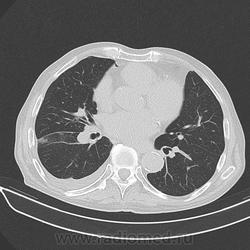

Мужчина 72 лет, лежит в кардиологии с ИБС.

Температуры нет, ОАК - Le - 10, сдвига формулы нет;  кашель редкий не продуктивный, иногда С ПРОЖИЛКАМИ КРОВИ.  Слабость, одышка.

Спустя несколько дней провели КТ  "для исключения онко-патологии".

p.s.  обратите внимание на зону аналогичного уплотнения в левом легком (видно на аксиалах).

Дайкомов не вижу, по джипегам расценил бы как ТЭЛА с субсегментарными инфарктами легких, достаточно характерная, как-бы "всепененная" структура.

,.. и гидротораксом справа, и (осумкованным/ограниченным-?) пневмотораксом (в переднем отделе, параперикардиально, опять же, справа)... Или пневмоперитонеум туда добрался... по неисповедимым своим путям?

я за центральный рак правого легкого

я думаю пневмоторакс может быть последствием "криво" выполненной плевральной пункции.

по моему есть узел в правом корне, н/долевого

За. А что слева подобное есть - тем более.